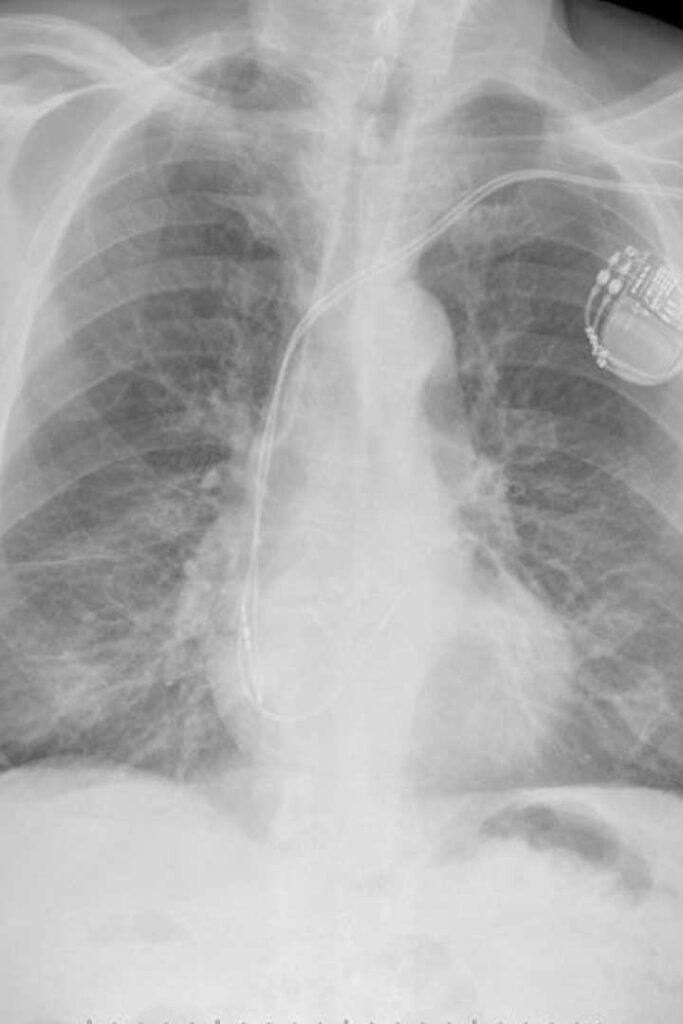

Chest X-Ray

TorchXrayVision

Detects and classifies thoracic abnormalities such as pneumonia, effusion, and cardiomegaly.

• AI-based triage & prioritization

• Early detection assists radiologists

• Multi-label prediction models

Univ. Montreal